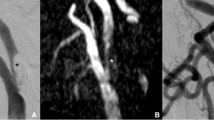

In all patients the stents could be recognised on native DSA mask images. Evaluation of the DSA series revealed 100% patency of the treated artery in 4 patients (patient 3, 5, 10, 12). In eight patients stenosis was recognised. In 4 of these cases, all of them treated for vertebral artery stenosis (patient 1, 2, 7, 11) it was possible to recognise the stent because of the proximal and distal markers but it was impossible to recognise the stent struts. Evaluation if the stent was completely deployed or not was impossible. Consequently differentiation of ISR or RS was impossible (Fig. 3). The other patients (4, 6, 8 and 9) were treated for middle cerebral artery stenosis. In these patients the stents were not superimposed by the skull base so the struts of the stents were visible. In these patients differentiation of ISR or RS was possible. In two patients (8 and 9) the reviewers recognised ISR while two patients (4 and 6) presented with RS. In patients 8 and 9 ISR was recognised because the stent was visible in the native mask as completely deployed while in subtracted images a stenosis was obvious (Fig. 4).

On DSA images the visibility of the stents is limited. In patient 7 a high grade stenosis (a) at the distal V4 level has been treated (b), a mild residual stenosis is obvious. Follow-up DSA (c) is without any change in comparison. Mask images of the DSA only show the markers (red arrow, d). Struts are not visible. FD-CTA evaluation (e, native sagittal MPR) clearly shows the residual stenosis (red arrow). Also the VRT reconstruction (h, red arrow) shows incomplete deployment of the stent. Contrast-enhanced MPR (f) displays the lumen perfused, residual narrowing is obvious (red arrow). In subtracted MIP reconstruction (g) the RS is nicely visible (red arrow). Additional artifact of the markers (grey arrow) is to be recognised. In axial MPR reconstructions artefacts of the markers (proximal markers, i native, j with contrast, i and j identical slice position) are visible at the aperture of the stent. The struts are perfectly visible (k, native images, red arrow). Contrast-enhanced MPR (l) nicely demonstrates homogeneous opacification of the stent lumen (K and L identical slice position)

In patient 8 a high grade MCA stenosis (a) was treated (b). In follow-up DSA (c) a mild stenosis is visible. The struts of the stent can be recognised in native DSA mask image (d, oblique view). Therefore ISR is obvious. In i.v. FD-CTA evaluation (e, native MPR) and also in VRT reconstruction (h) the stent is completely deployed. Notice artefacts of the markers (e, red arrows). The contrast-enhanced MPR reconstruction (f) nicely shows material (red arrows) adjacent to the inner surface of the stent. This leads to the visualisation of a stenosis in subtracted MIP reconstruction (g, red arrow). In axial MPR reconstructions artefacts of the markers (proximal markers, i native, j with contrast, i and j identical slice position) are visible at the aperture of the stent (i, red arrows), but in this case not as severely as in Fig. 3. Native and contrast-enhanced MPR at the side of stenosis (k native, l with contrast material) nicely demonstrates material with a half-moon shape adjacent (black arrow) to the inner stent lumen (k and l identical slice position). The perfused lumen is perfectly visible (red arrow)